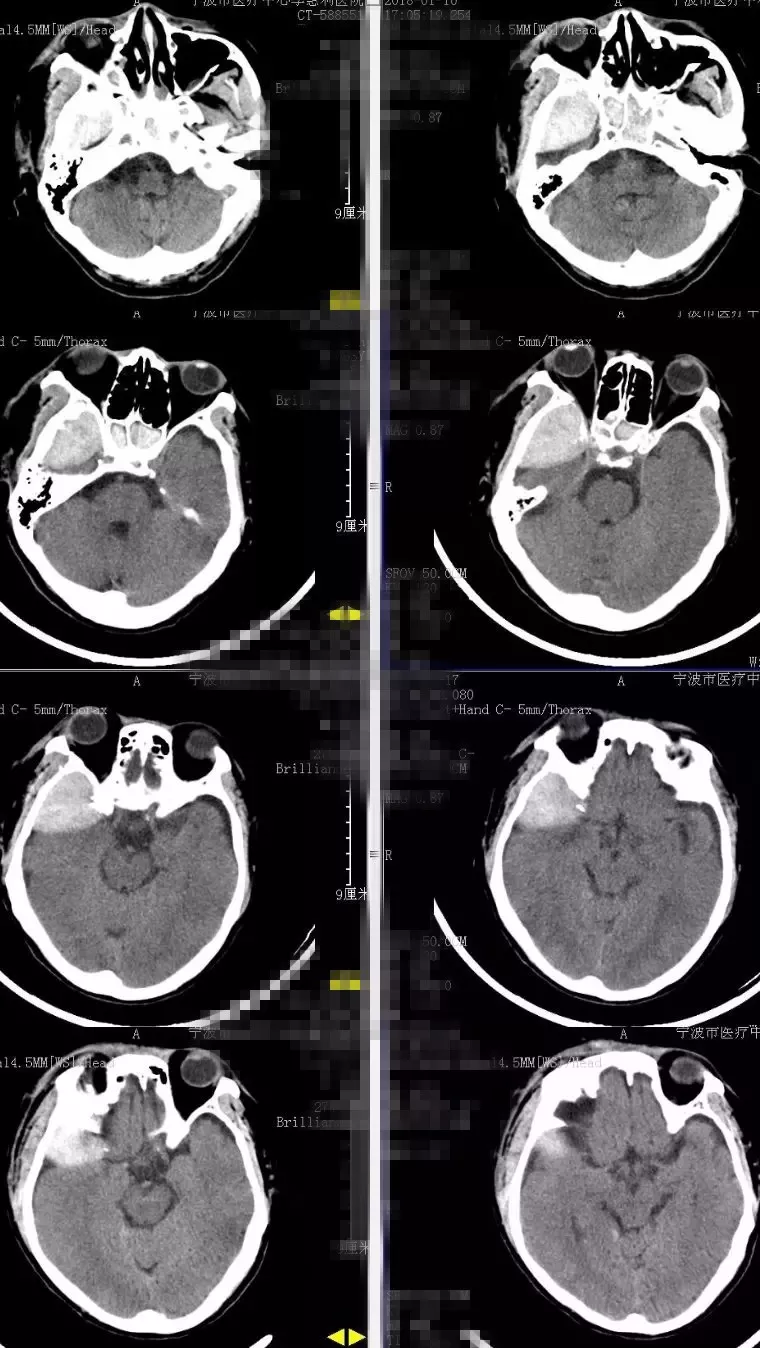

辅助检查:2018-1-10复查头部及胸部CT:右颞部硬膜外血肿。右侧颞骨、颧弓骨折,右侧颅底多发骨折(图1)。右侧液气胸,胸腔引流管在位。右侧多发肋骨骨折。右肱骨正侧位片:右侧肱骨下端粉碎性骨折。

图1. 2018-1-10入院时头CT:右颞部硬膜外大血肿。右侧颞骨、颧弓骨折,右侧颅底多发骨折。